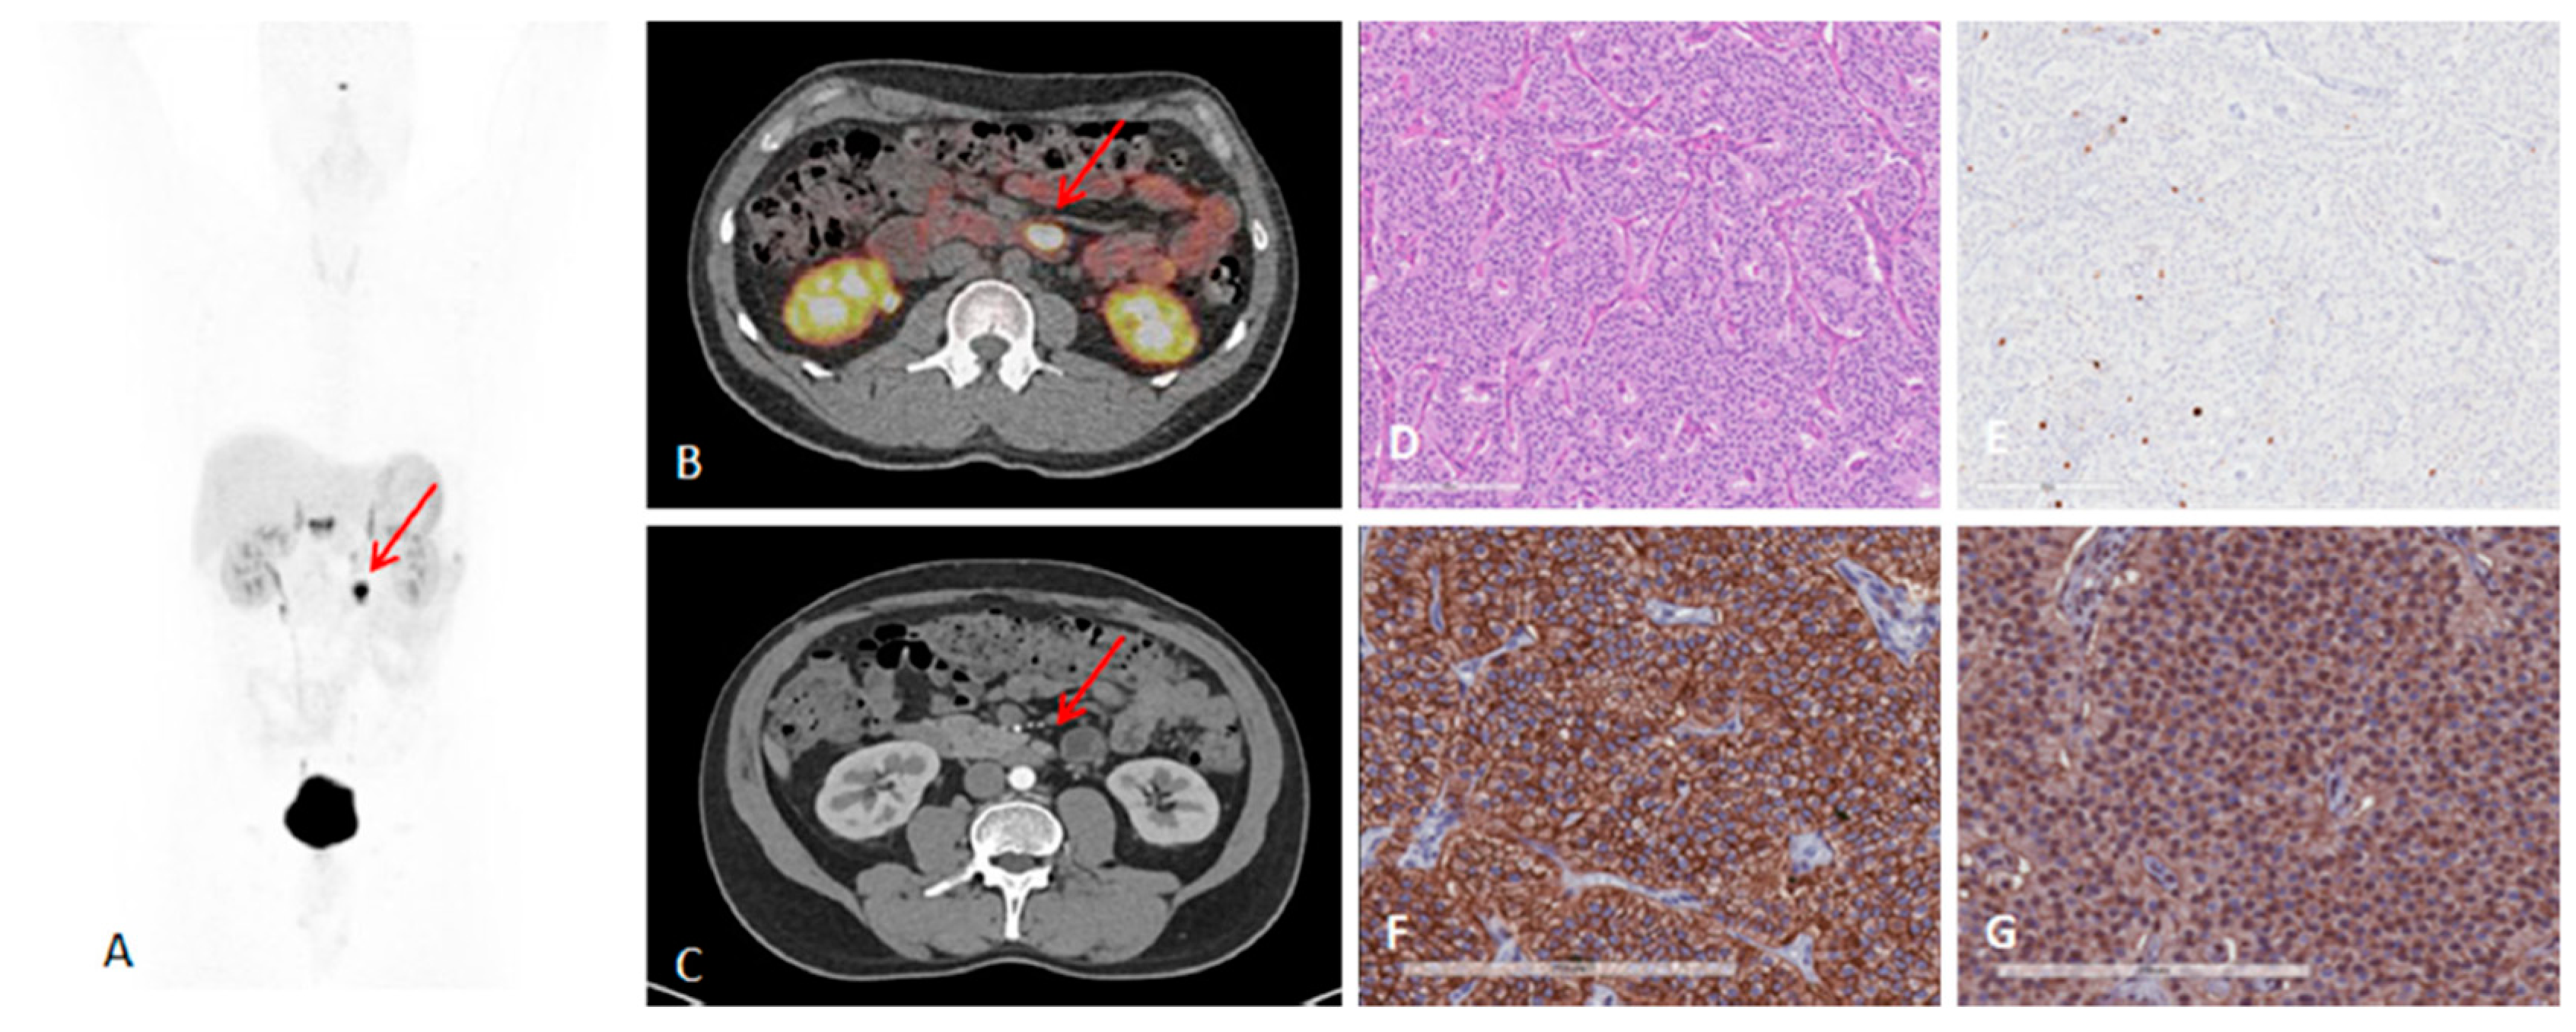

Figure 4.

A 41-year-old man with metastatic lymph nodes on [68Ga]Ga-DOTA-TATE PET/CT. He had undergone previous surgery for pancreatic NET (patient 5). Mesenteric lymph node from primary pancreatic NET was found with probe with TBR of 3.4 for this 0.8 cm lesion (WHO grade 1). (A) [68Ga]Ga-DOTA-TATE PET maximum intensity projection image showing mesenteric/duodenal lesion in segment 3 (red arrow) and multiple retroperitoneal lymph nodes. (B) [68Ga]Ga-DOTA-TATE PET/CT image showing mesenteric mass with SUVmax of 72.8 (red arrow). (C) Arterial phase CT showing corresponding mesenteric mass (red arrow). (D) Representative hematoxylin and eosin staining of tumor showing NET in lymph node, WHO grade 1. (E) Representative immunohistochemistry for MIB-1 staining showing <2% of cells positive. (F) Immunohistochemistry for SSTR2 showing representative image for score 3 (membranous pattern of SSTR2 staining in >50% of tumor cells) (original magnification, ×20). (G) Immunohistochemistry for SSTR5 showing representative image of tumor with >10% of tumor cells positive (original magnification, ×20). Reproduced from [15].